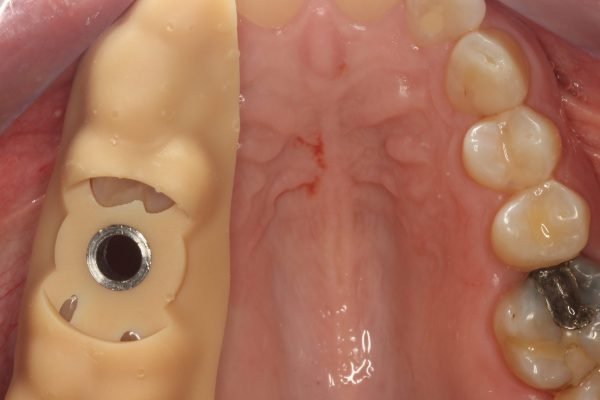

Cirugía Guiada por Ordenador

Durante la cirugía, se utilizan guías quirúrgicas personalizadas basadas en esta planificación digital. Estas guías ayudan a posicionar el implante en el lugar exacto determinado en la planificación, asegurando que esté perfectamente alineado y rodeado de suficiente hueso, lo cual es crucial para su integración y estabilidad a largo plazo. Además, esta precisión garantiza que el implante esté en la posición óptima para recibir la prótesis dental, lo que mejora la funcionalidad y estética del resultado final.